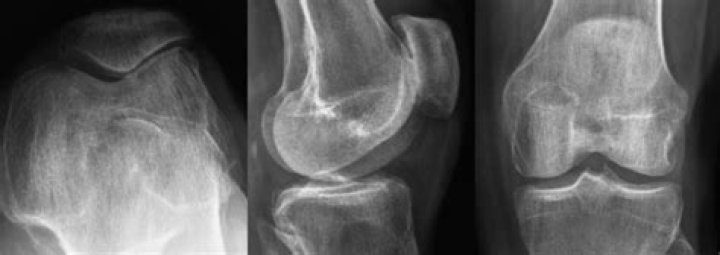

Will an xray show a torn meniscus?

Because a torn meniscus is made of cartilage, it won't show up on X-rays. But X-rays can help rule out other problems with the knee that cause similar symptoms. MRI . This uses a strong magnetic field to produce detailed images of both hard and soft tissues within your knee.